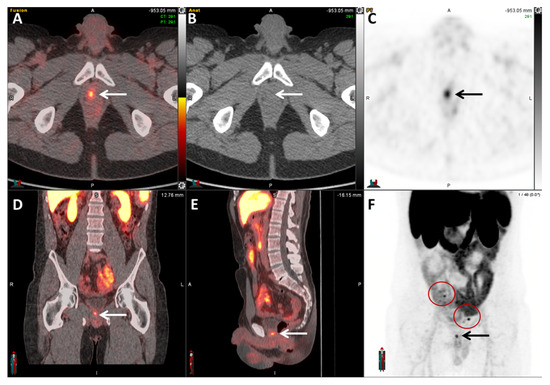

- Pienta, K.J.; Gorin, M.A.; Rowe, S.P.; Carroll, P.R.; Pouliot, F.; Probst, S.; Saperstein, L.; Preston, M.A.; Alva, A.S.; Patnaik, A.; et al. A Phase 2/3 Prospective Multicenter Study of the Diagnostic Accuracy of Prostate Specific Membrane Antigen PET/CT with 18F-DCFPyL in Prostate Cancer Patients (OSPREY). J. Urol. 2021, 206, 52–61. [Google Scholar] [CrossRef]

- Morris, M.J.; Rowe, S.P.; Gorin, M.A.; Saperstein, L.; Pouliot, F.; Josephson, D.; Wong, J.Y.C.; Pantel, A.R.; Cho, S.Y.; Gage, K.L.; et al. Diagnostic Performance of 18F-DCFPyL-PET/CT in Men with Biochemically Recurrent Prostate Cancer: Results from the CONDOR Phase III, Multicenter Study. Clin. Cancer Res. Off. J. Am. Assoc. Cancer Res. 2021, 27, 3674–3682. [Google Scholar] [CrossRef]

- Keam, S.J. Piflufolastat F 18: Diagnostic First Approval. Mol. Diagn. Ther. 2021, 25, 647–656. [Google Scholar] [CrossRef]

- Ulaner, G.A.; Thomsen, B.; Bassett, J.; Torrey, R.; Cox, C.; Lin, K.; Patel, T.; Techasith, T.; Mauguen, A.; Rowe, S.P.; et al. 18F-DCFPyL PET/CT for Initially Diagnosed and Biochemically Recurrent Prostate Cancer: Prospective Trial with Pathologic Confirmation. Radiology 2022, 305, 419–428. [Google Scholar] [CrossRef]

- Rowe, S.P.; Macura, K.J.; Mena, E.; Blackford, A.L.; Nadal, R.; Antonarakis, E.S.; Eisenberger, M.; Carducci, M.; Fan, H.; Dannals, R.F.; et al. PSMA-Based [18F]DCFPyL PET/CT Is Superior to Conventional Imaging for Lesion Detection in Patients with Metastatic Prostate Cancer. Mol. Imaging Biol. 2016, 18, 411–419. [Google Scholar] [CrossRef] [PubMed]